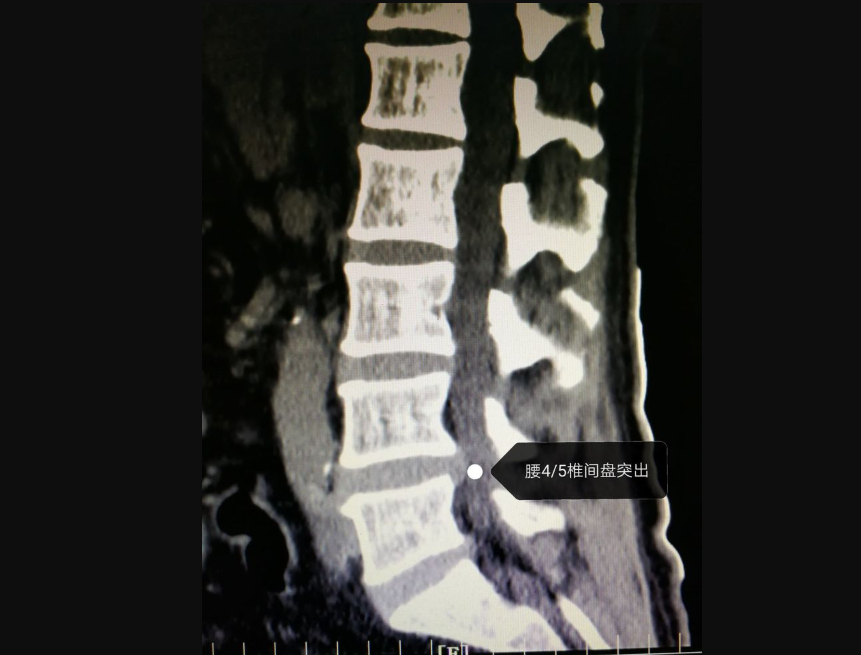

腰部正常的CT可见相邻椎体形状、大小一致、密度均匀的软组织影。而异常的腰部CT,如腰椎间盘病变,在CT图像上可看到纤维环钙化椎间盘膨出、突出、脱出,神经根受压移位或湮没,突出的椎间盘钙化。